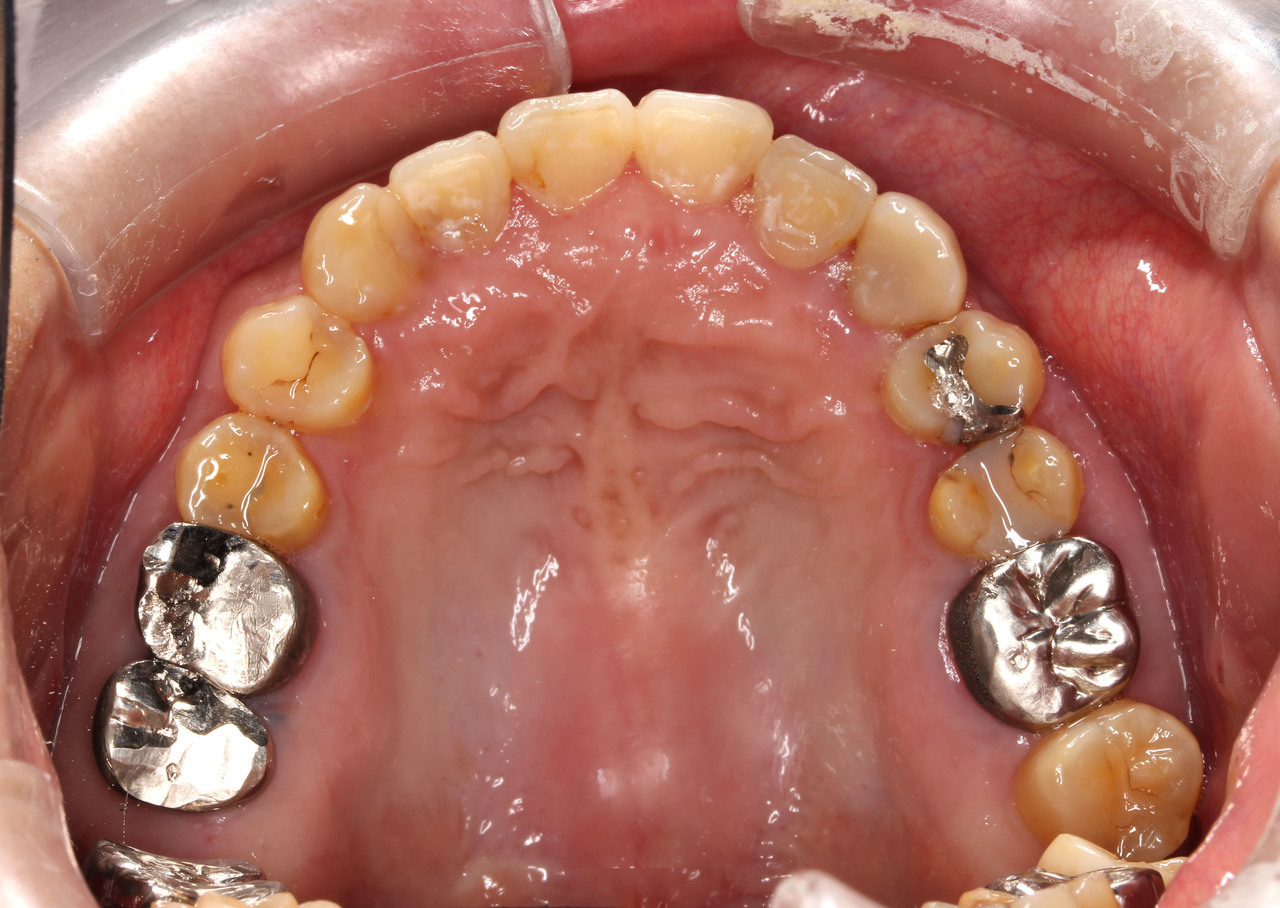

症例3

• 主訴:44歳「ガミースマイルを治したい」という女性で、笑ったとき歯ぐきが出てしまうのがお悩みということでした。

• 矯正方法:マルチブラケット装置(ハーフリンガル矯正)により矯正治療を行いました。

• 抜歯部位:上左右第一小臼歯

• 矯正費用:90万~110万円(税込)

• 動的治療期間:2年

• 副作用リスク:副作用リスクについてはこちらのページをご覧ください。

• ※矯正治療は保険対象外の自由診療となります。